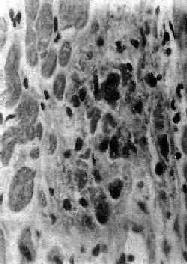

图8-19 Aschoff小体 主由Anitschkow细胞、Aschoff巨细胞和淋巴细胞等组成,中心部常有纤维素样坏死物 3.瘢痕期(愈合期) 细胞成分减少,出现纤维母细胞,产生胶原纤维,并变为纤维细胞。整个小体变为梭形小瘢痕。此期经过约2~3个月。 本病病变的自然经过为4~6个月,但常反复发作,因此,新旧病变常同时并存。 发生在浆膜的风湿病变主要为浆液性和(或)纤维素性炎症。

二、基本病变风湿热时,病变可累及全身结缔组织,特别是心脏各层均可被累及;小动脉亦往往被侵犯。病变发展过程大致可分为三期: 1.变质渗出期 开始是结缔组织纤维发生粘液样变性,可见胶原纤维肿胀(原纤维间水肿,intermicrofibrillary edema),结缔组织基质内蛋白多糖(主要为氨基葡聚糖)增多。HE染色呈嗜碱性,甲苯胺蓝染色呈异染性,即呈红色。继而肿胀的胶原纤维断裂、崩解成无结构的颗粒状物,与基质中的氨基葡聚糖混合在一起,加上免疫球蛋白、有时还有纤维蛋白沉积,致使病灶的染色性状颇似纤维蛋白,因此称为纤维素样变性(纤维素样坏死)。此外,病灶中还有少量浆液和炎症细胞(淋巴细胞、个别中性粒细胞和单核细胞)浸润。此期持续约1个月。 2.增生期 亦称为肉芽肿期(granulomatous phase ),其特点是形成具有疾病特征性的风湿性肉芽肿,即Aschoff小体(Aschoff body),对本病具有诊断意义。 Aschoff 小体体积颇小,一般显微镜下才能看见(图8-19),多发生于心肌间质、心内膜下和皮下结缔组织;心外膜、关节和血管等处少见。在心肌间质内者多位于小血管旁,略带圆形或梭形,其中心部为纤维素样坏死灶,周围有各种细胞成分:①Anitschkow细胞:胞浆丰富,嗜碱性,核大,呈卵圆形、空泡状。染色质集中于核的中央,核的横切面状似枭眼;纵切面上,染色质状如毛虫。②Aschoff巨细胞(Aschoff giant cell):含有1~4个泡状的核,与Anitschkow细胞相似,胞浆嗜碱性。以上两种细胞的来源尚有争论,但现代标记技术证明其为巨噬细胞源性。③小体内还有少量淋巴细胞(主要为T细胞)和个别中性粒细胞。此期经过约2~3个月。